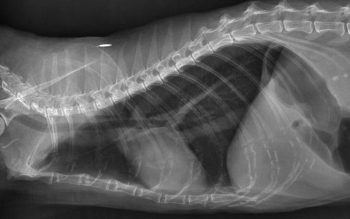

In BAL samples from healthy cats, again, alveolar macrophages are present in large numbers. However, in most studies, feline BAL samples frequently contained large numbers of eosinophils, and they may even be the predominant BAL cell type. A large proportion of neutrophils may also be present in clinically healthy cats. Finer classification of feline lower airway disease is, therefore, challenging. Crudely, our diagnosis must rely on the presence of clinical signs, demonstration of supportive findings, such as radiographic changes and airway cytology, and exclusion of various infectious (or occasionally neoplastic) causes.

However, a variety of clinical presentations may be appreciated; some cats have a mild but persistent cough for months to years, others rarely cough, but show continuous laboured, wheezy breathing, and a minority of cats lead a normal symptom-free life, but suffer intermittent, sudden onset severe respiratory distress, which, in some cases, may be life-threatening. These latter presentations may be the ones that most closely resemble asthma in people. Interestingly, radiographic changes may sometimes be subtle or lacking in this subset of feline patients, supporting a theory dynamic reversible bronchoconstriction is occurring in response to some stimulus.